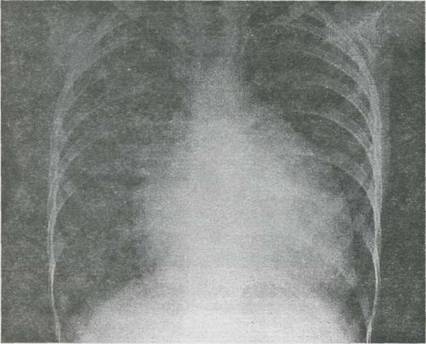

scazuta. Auscultatia cordului nu este patognomonica pentru boala. Suflul de ejectie, cu maximum de auscultatie īn spatiul II-III intercostal stāng, care se transmite īn spate, īn ambele parti, este de fapt suflul de stenoza pulmonara. īn caz de atrezie pulmonara, suflul poate lipsi. Cu cāt stenoza este mai strānsa, cu atāt durata suflului este mai scurta, fiind doar protosistolic. Radiografia cardiopulmonara nu este totdeauna atāt de tipica precum īn descrierile clasice si cordul "īn sabot" se vede rar. Hipovascularizatia cāmpurilor pulmonare si un cord de dimensiuni normale constituie caracteristica cea mai pregnanta a examenului radiologie. Se constata silueta cordului mai mult sau mai putin modificata, cu vārful ridicat deasupra diafragmului (hipertrofia ventriculului drept), dextropozitia crosei aortei (25% din cazuri) sau arc mijlociu concav (hipoplazia arterei pulmonare). Daca toate aceste elemente sunt bine exprimate, umbra cordului a fost comparata cu un sabot. ECG este departe de a fi caracteristic, domina hipertrofia ventriculului drept. Alte examene de laborator obiectiveaza poliglobulia (6-7 milioane de hematii/mm3 cu hemoglobina 20g/100ml si hematocrit de 50-60%). īn timpul crizelor anoxice se obiectiveaza acidoza metabolica. Echografia unidimensionala ca si echografia bidimensionala sunt de mare utilitate pentru diagnostic. Aorta "calare" pe septul inter-ventricular ca si continuitatea aortico-mitrala sunt usor de obiectivat īn ambele tehnici. Sectiunea parasternala ax mare sau cea subxifoidiana evidentiaza comunicarea interventriculara si discontinuitatea aorto-septala precum si dilatatia si hipertrofia ventriculului drept.

Fig. 9-16. Miocardita acuta virala la un sugar īn vārsta de 7 luni. Radiografie cardiopulmonara.

A. Cardiomegalie importanta cu hipertrofie ventriculara stānga.

B. Cord de dimensiuni normale dupa 16 saptamāni de tratament.